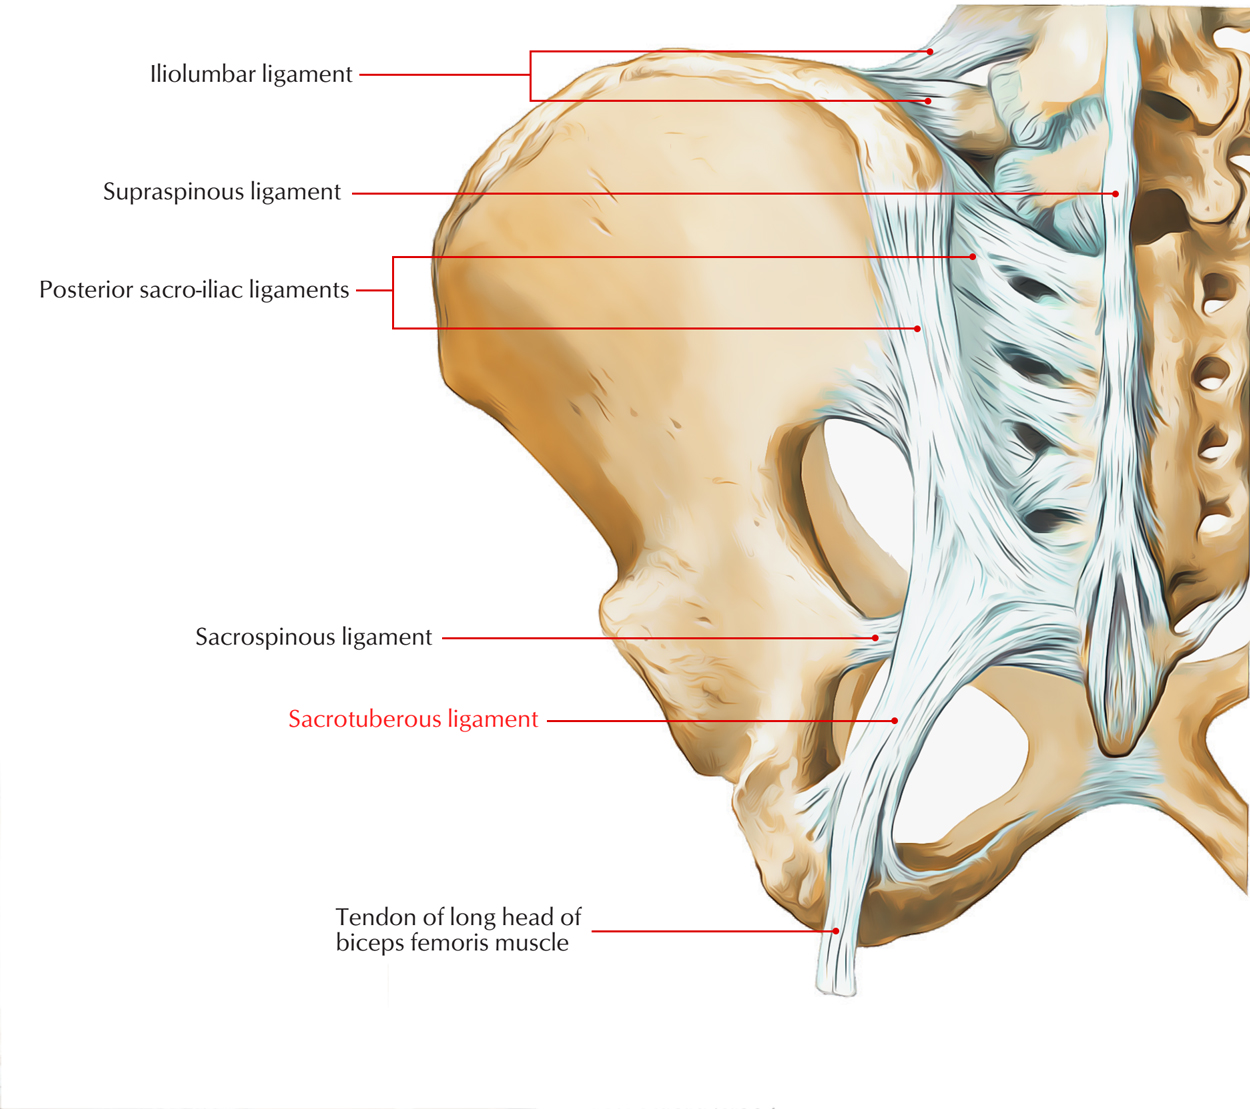

Lumbar instability as an etiology of low back pain and its treatment by prolotherapy: A review - Ross A. Hauser, Danielle Matias, David Woznica, Benjamin Rawlings, Barbara A. Woldin, 2022